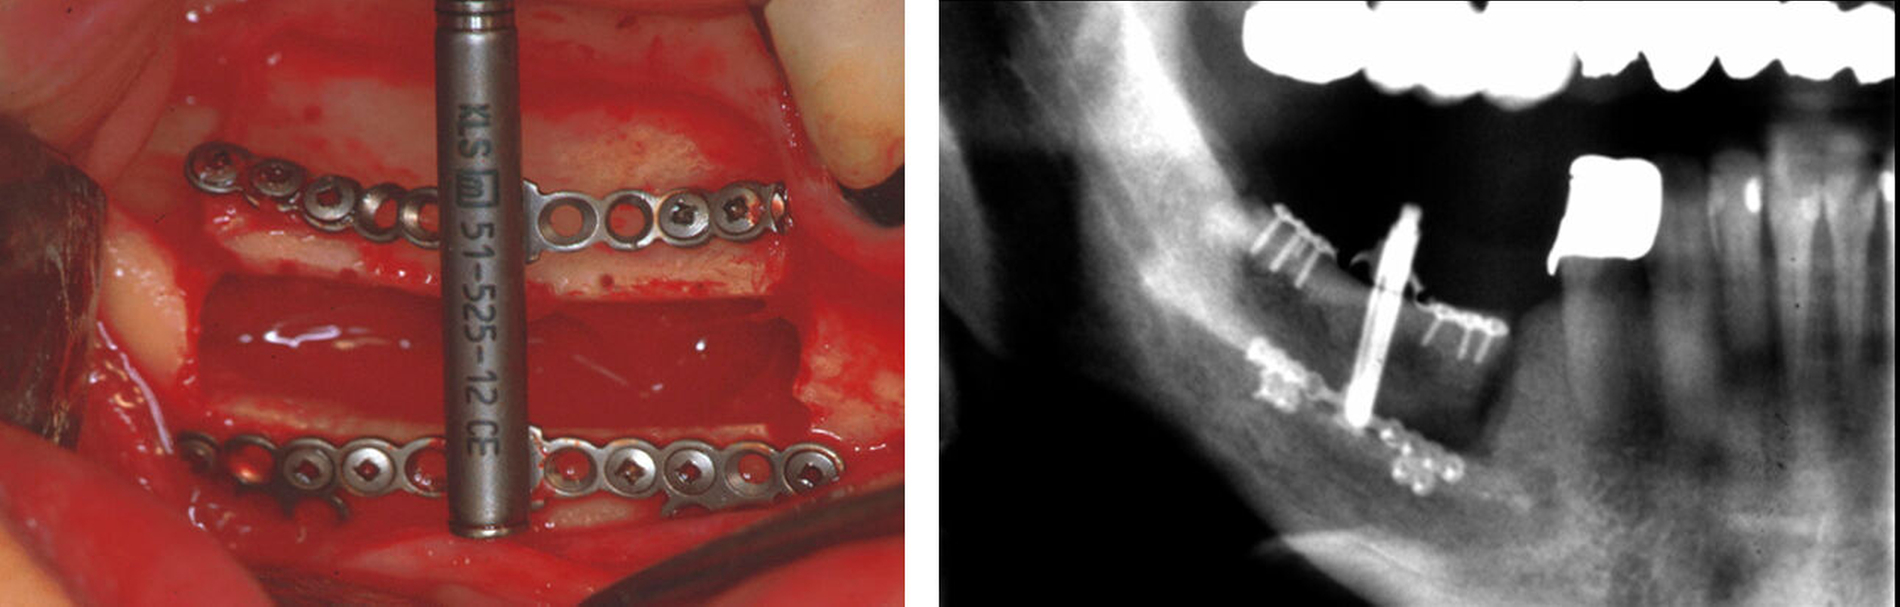

Die chirurgische Umsetzung mithilfe von individuell hergestellten Bohr- und Sägeschablonen ermöglicht die geplanten Bohrungen mit einer Fehlerabweichung von < 1 mm und das Setzen der Osteotomielinie mit einer Abweichung von weniger als 4° von der geplanten Achse [Vanesa et al., 2021]. In Anbetracht der beengten knöchernen Verhältnisse von Kleinkindern stellt diese Genauigkeit einen enormen Vorteil dar (Abbildung 3).

Nach der Herstellung eines 3D-Modells können die Fußplatten des Distraktors bereits präoperativ optimal an die Anatomie des Kiefers oder des Schädelknochens angepasst werden, wodurch sich wiederum die Passgenauigkeit und die Stabilität erhöhen bei gleichzeitiger Verkürzung der OP-Zeit. Die vereinfachte Applikation des Distraktors ermöglicht in vielen Fällen die Durchführung der Operation von intraoral mit zusätzlichen transbukkalen Bohrhilfen, da die direkte Aufsicht auf die Osteotomie durch die vorhandene Schablonenführung wegfällt (Abbildung 3F). Unterstützt wird dieses Vorgehen durch die transorale endoskopische Darstellung der Osteotomien und Bohrungen (Abbildung 4).

Neue piezochirurgische abgewinkelte Sägesysteme vereinfachen zudem die kontrollierte Osteotomie. Hauptnachteil der virtuellen Planung ist selbstverständlich die Notwendigkeit einer Computertomografie mit der einhergehenden Strahlenexposition. Dazu kommt, dass bei Kleinkindern diese Untersuchung oftmals in Narkose erfolgen muss, was aufgrund der veränderten Anatomie mit möglicher Kompromittierung des Luftwegs weitere anästhesiologische Probleme nach sich ziehen kann.